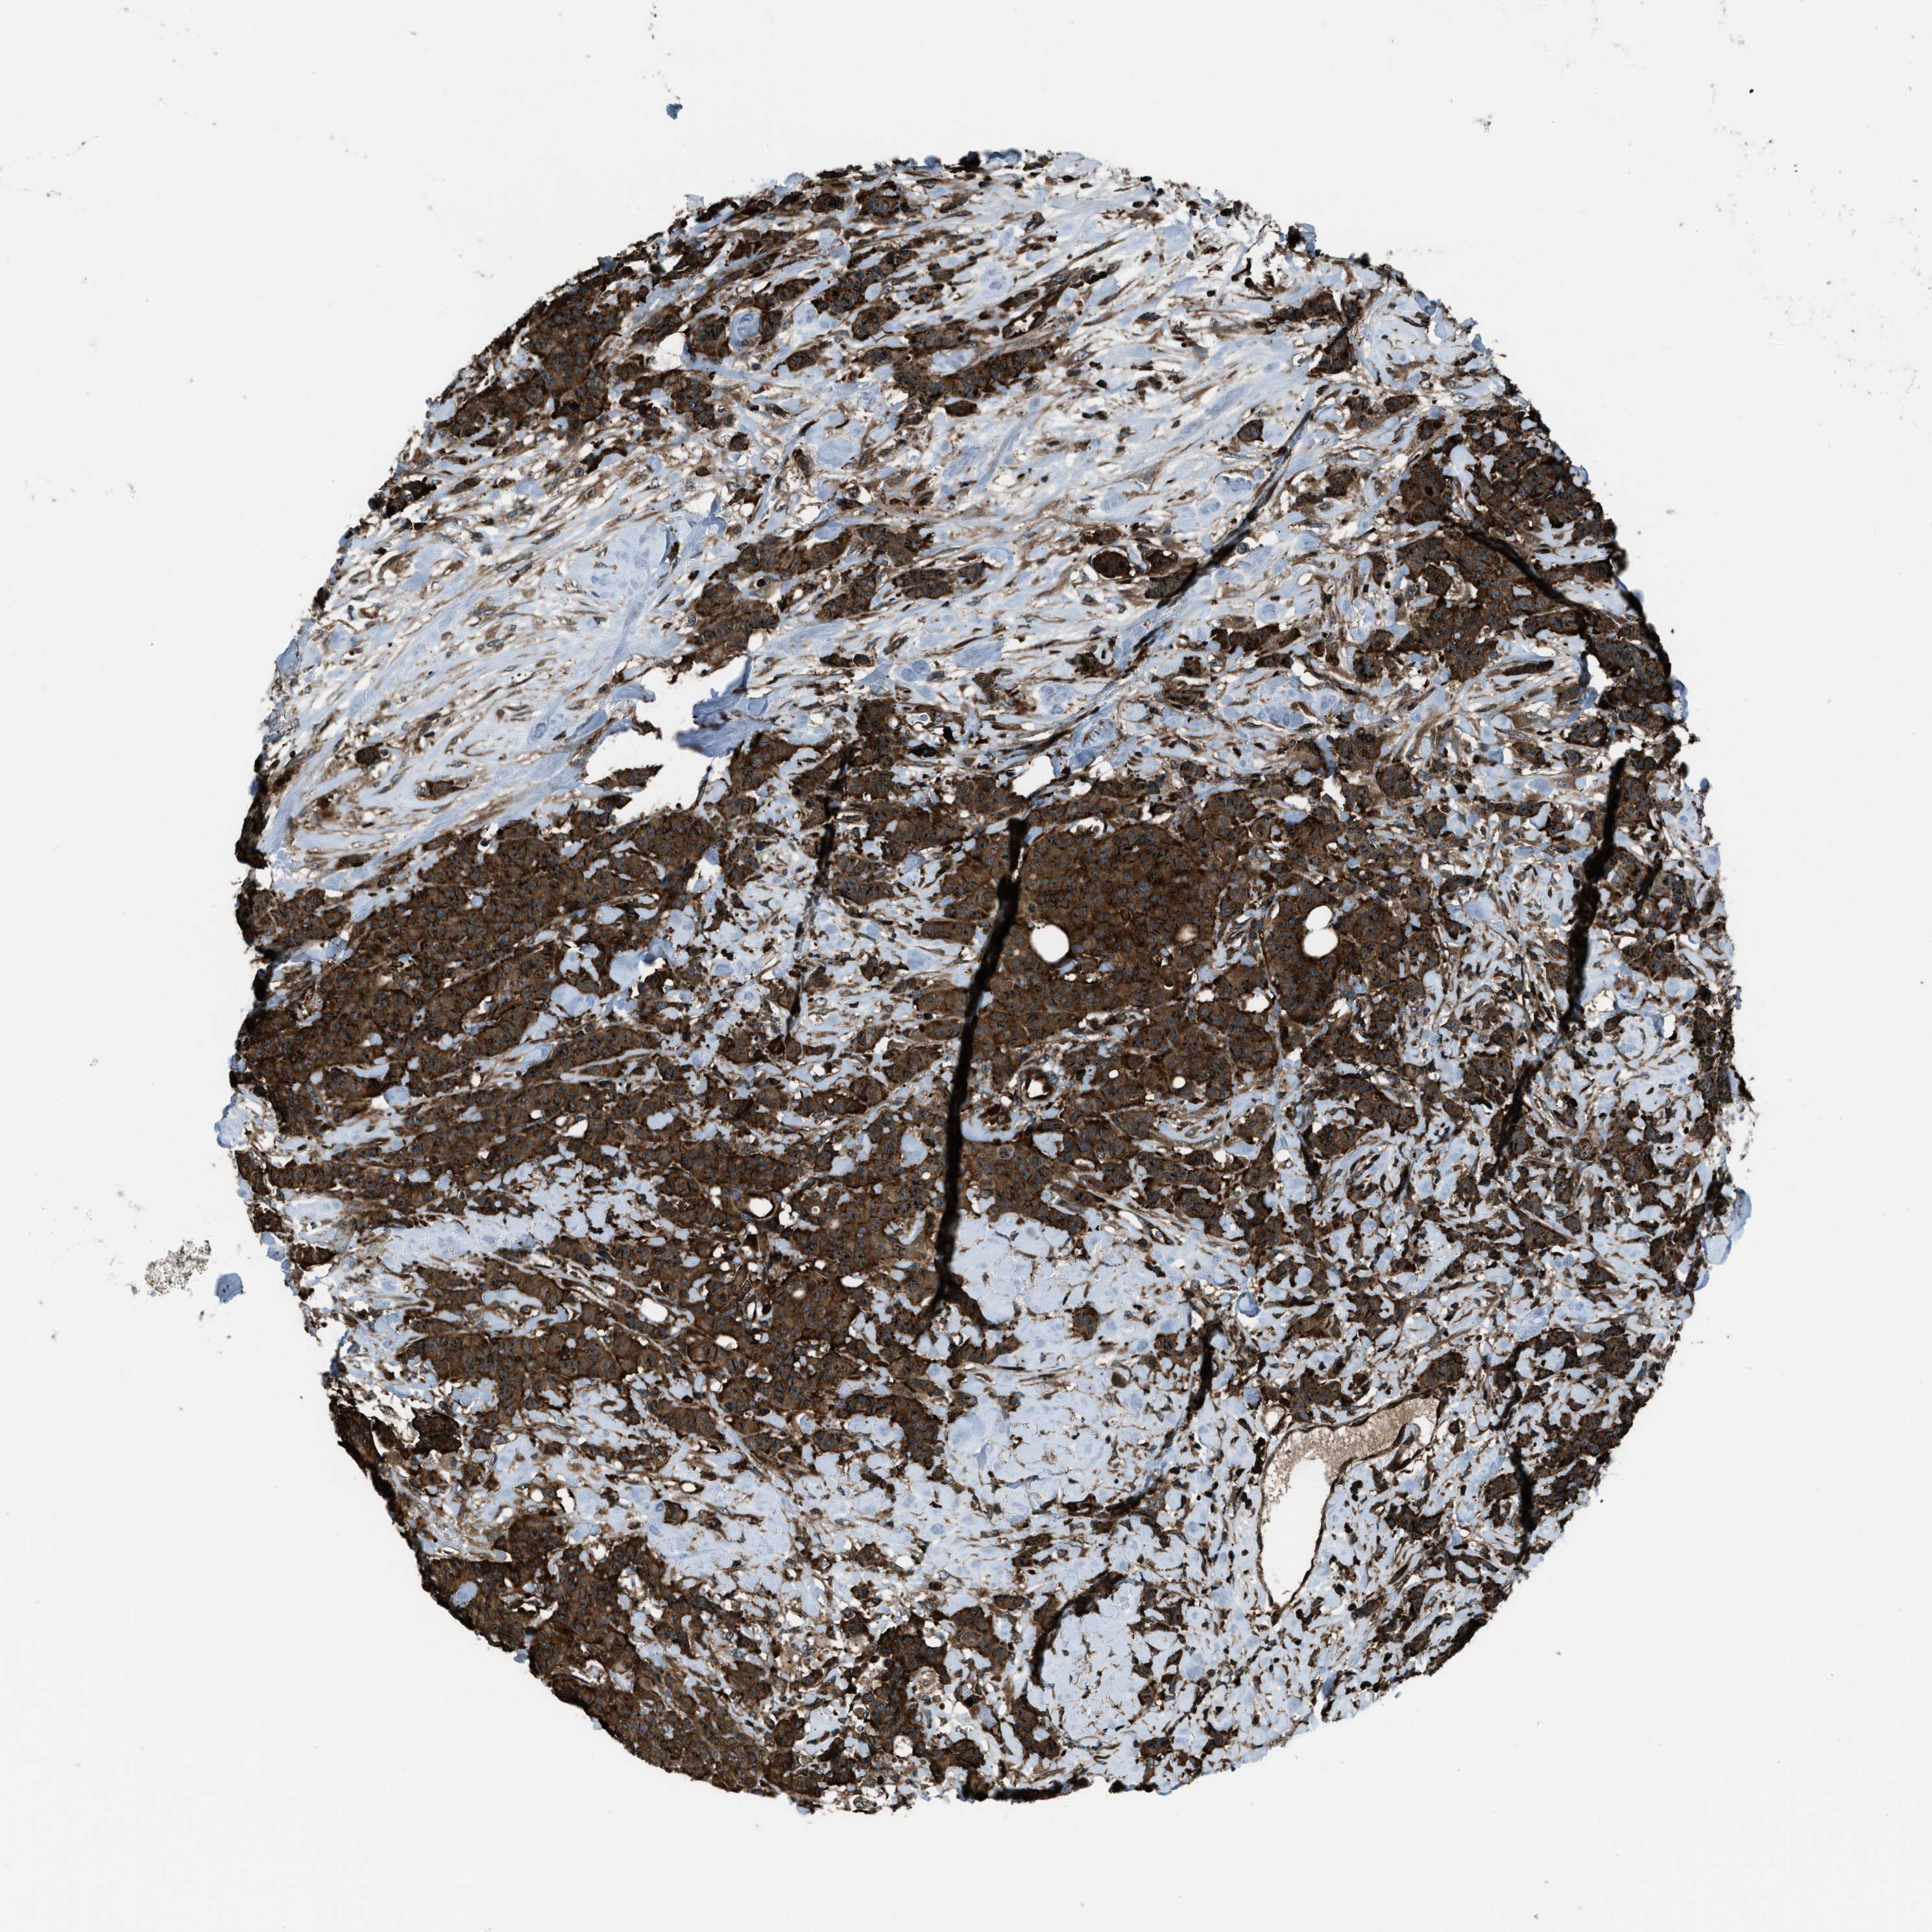

CANCER BREAST CANCER Show tissue menu

BRCA TCGA BRCA VALIDATION PROTEIN EXPRESSION